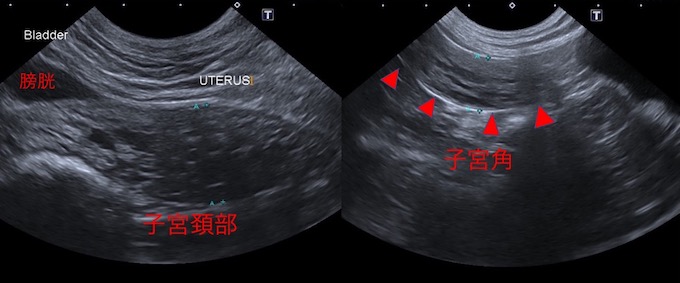

当院での画像検査所見です。

超音波検査画像です。

子宮角〜子宮頚部まで子宮内部には占拠性病変が認められ、子宮腫瘍の可能性が考えられました。左右の卵巣には異常所見は認められませんでした。